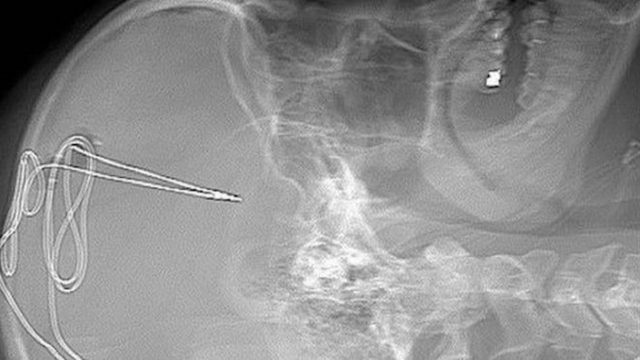

Un grupo de médicos en Estados Unidos ha desarrollado un “marcapasos cerebral” para combatir la crisis de opioides en el país. Cuatro personas ya se han sometido a la operación con la intención de mejorar su calidad de vida. También te puede interesar: Primera farmacéutica recibe multa por responsabilidad en crisis de opioides Los opioides … Sigue leyendo Desarrollan ‘marcapasos cerebral’ para combatir adicciones